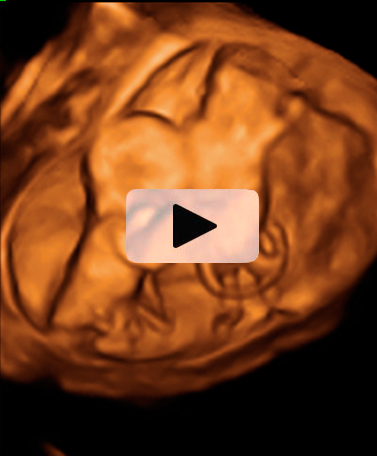

Vemos tres planos de un embarazo de trillizos en ecografía 2D en diferentes cortes de imagen. Lo que vemos en 3D es lo que los ecografistas conocen como "un queso", es decir el embarazo visto en tres dimensiones desde una perspectiva determinada. Lo que realmente esconde ese peculiar queso es un embarazo de trillizos: un feto independiente, separado de sus hermanos por una membrana.

Los gemelos se desarrollan en dos bolsas diferentes. En otro corte de la imagen, se ve un embrión independiente separado por una membrana de los otros dos hermanos, que se sitúan en bolsas independientes.